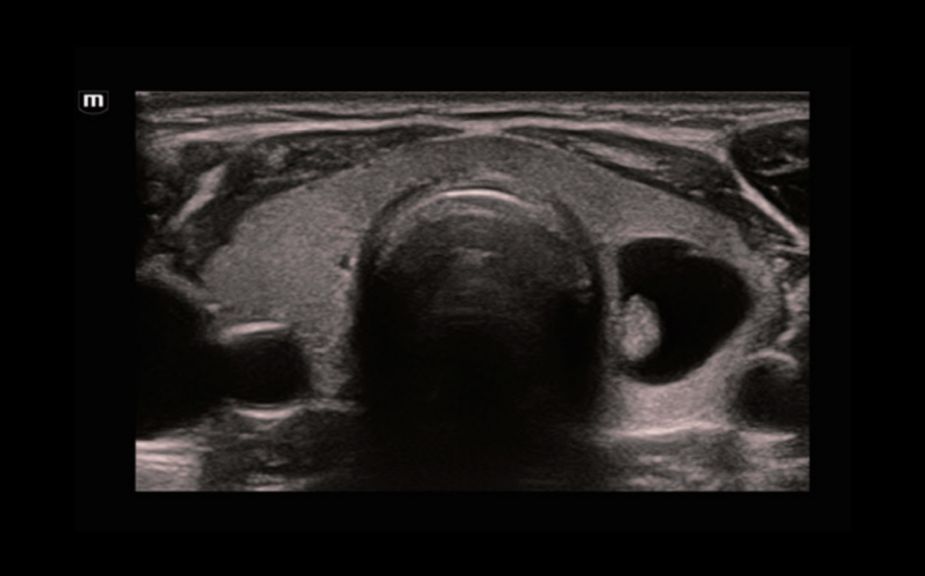

–ö–Θ–Θ–½–‰: –Φ–Β―²–Α―¹―²–Α―²–Η―΅–Β―¹–Κ–Η–Ι ―Ä–Α–Κ –Ω–Β―΅–Β–Ϋ–Η

–ö–Θ–Θ–½–‰: –Ω–Β―Ä―³―É–Ζ–Η―è –Α–¥–Β–Ϋ–Ψ–Φ―΄ ―â–Η―²–Ψ–≤–Η–¥–Ϋ–Ψ–Ι –Ε–Β–Μ–Β–Ζ―΄